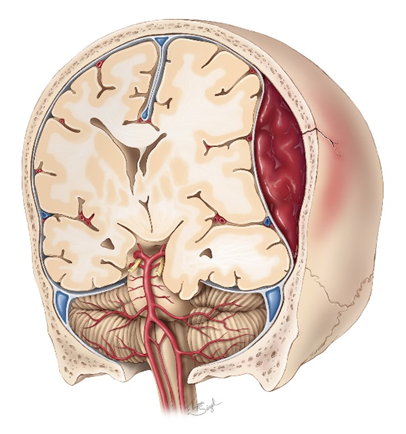

2/ Máu tụ ngoài màng cứng

Máu tụ ngoài màng cứng là tình trạng máu tích tụ trong khoang giữa xương sọ và màng cứng, một khoang vốn không tồn tại trong điều kiện bình thường nên được gọi là khoang ảo. Khi xảy ra chảy máu, áp lực của dòng máu sẽ bóc tách màng cứng ra khỏi mặt trong của xương sọ, tạo thành một khối máu tụ có áp lực cao [5]. Khối máu này không chỉ chiếm chỗ mà còn nhanh chóng làm tăng áp lực nội sọ, từ đó chèn ép trực tiếp lên nhu mô não và các cấu trúc lân cận, gây rối loạn chức năng thần kinh.

Về cơ chế bệnh sinh, nguyên nhân thường gặp nhất là chấn thương vùng thái dương – nơi xương sọ tương đối mỏng và dễ gãy. Khi xương bị vỡ, động mạch màng não giữa chạy ngay phía dưới có thể bị rách, dẫn đến chảy máu ồ ạt. Do nguồn chảy máu là động mạch nên tốc độ chảy nhanh và áp lực lớn, khiến khối máu tụ tăng kích thước rất nhanh chỉ trong thời gian ngắn. Điều này giải thích vì sao bệnh có thể diễn tiến đột ngột và nguy hiểm. Ngoài ra, trong một số trường hợp hiếm hơn, máu tụ ngoài màng cứng có thể do tổn thương tĩnh mạch hoặc xoang tĩnh mạch màng cứng, tuy nhiên diễn tiến thường chậm hơn [4].

Về lâm sàng, dấu hiệu điển hình là “khoảng tỉnh”, một đặc điểm rất quan trọng giúp định hướng chẩn đoán [3]. Sau chấn thương, bệnh nhân có thể mất ý thức thoáng qua do chấn động não, sau đó tỉnh lại và có vẻ ổn định trong một khoảng thời gian ngắn. Tuy nhiên, khi khối máu tụ tiếp tục lớn dần, áp lực nội sọ tăng lên sẽ làm tình trạng bệnh nhân nhanh chóng xấu đi. Người bệnh bắt đầu xuất hiện đau đầu tăng dần, buồn nôn và nôn, giảm mức độ ý thức. Khi tình trạng chèn ép tiến triển, có thể xuất hiện các dấu thần kinh khu trú như giãn đồng tử cùng bên tổn thương do chèn ép dây thần kinh III, kèm theo yếu hoặc liệt nửa người đối bên [5]. Nếu không được phát hiện và can thiệp kịp thời, khối máu tụ có thể gây tụt kẹt não – một biến chứng cực kỳ nguy hiểm – và dẫn đến tử vong.